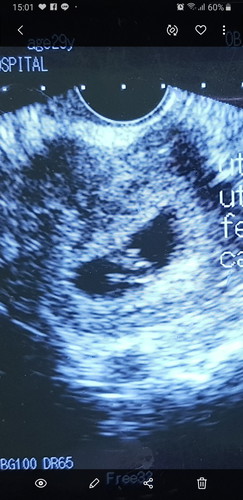

แบบนี้ทีโอกาสท้องแฝดไหมคะ

คือเอาตรงๆเลย เราดูไม่รู้เรื่องอะค่ะ 5555 หมอครั้งนี้ที่ไปก้ไม่ใช่หมอประจำ หมอบอกแค่ว่ายังเล็กมาก... แต่ท้องเราปูดเร็วมากค่ะ เลยสงสัย แล้วเราจะรู้ว่าแฝดได้เร็วสุดเมื่อไหร่คะ ขอบคุณค่ะ

ไม่น่าจะแฝดนะคะ ถ้าแฝดต้องมี2ถุง สรีระแม่บอกไม่ได้ว่าแฝดไหมค่ะ

พี่ที่เราสนิทด้วย ซาวด์ทางช่องคลอด เจอว่าแฝดตอน 6 สัปดาห์จ้า